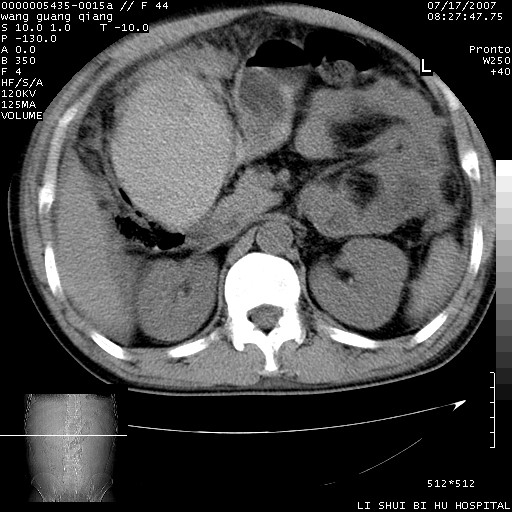

以下是引用dyqct在2007-7-18 10:46:00的发言:[br]胆囊明显增大,壁增厚,明显强化;后下方见大片高密度区,ct值68hu,无强化,周围见多数条纹状高密度影,边界不清。双膈下间隙、肝肾隐窝见带状及片状低密度区。[br]右侧胸壁后缘亦见新月形水样密度区。[br]考虑:1、急性胆囊炎伴周围出血;[br] 2、少量腹水、右侧少量胸腔积液。[br][br][本贴已被 dyqct 于 2007-7-18 10:48:47 修改过]